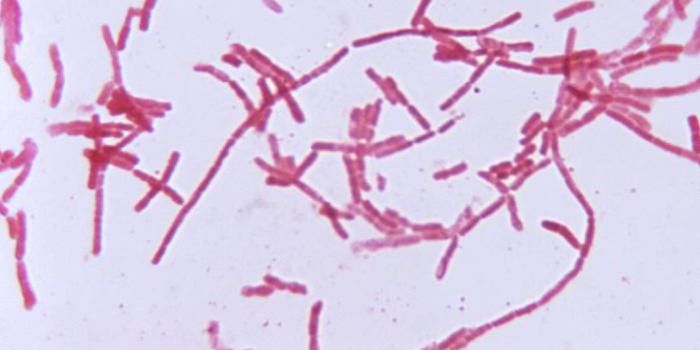

APR 19, 2016Health & MedicineMycobacterium tuberculosis, the bacterial species behind tuberculosis infections, is the leading cause of bacterial deat ...